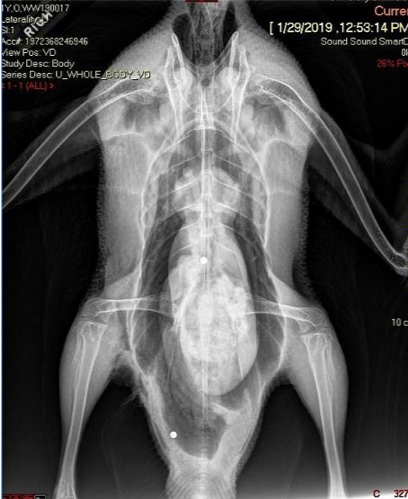

The next day the goose was placed under general anesthesia for radiographs (X-rays) to check for internal damage from the gunshot – often there is more than one pellets involved. Low and behold, two other pellets were found! The goose also suffered a wing and pelvic fracture (see pictures below), either from being shot or from falling while flying. To stabilize the wing, a bandage called a figure-8 wrap was placed. Luckily, the fracture was just of the ulna and not the radius as well, so no surgery was needed. The pelvis was still aligned appropriately and the goose was walking normally, so no further intervention was needed.

Weeks of medical care and bandaging paid off! By three weeks, the wound was almost completely healed and it was time to recheck the ulnar and pelvic fractures. Both appeared to be healing well so the bandage around the wing was removed (see recheck X-ray below).